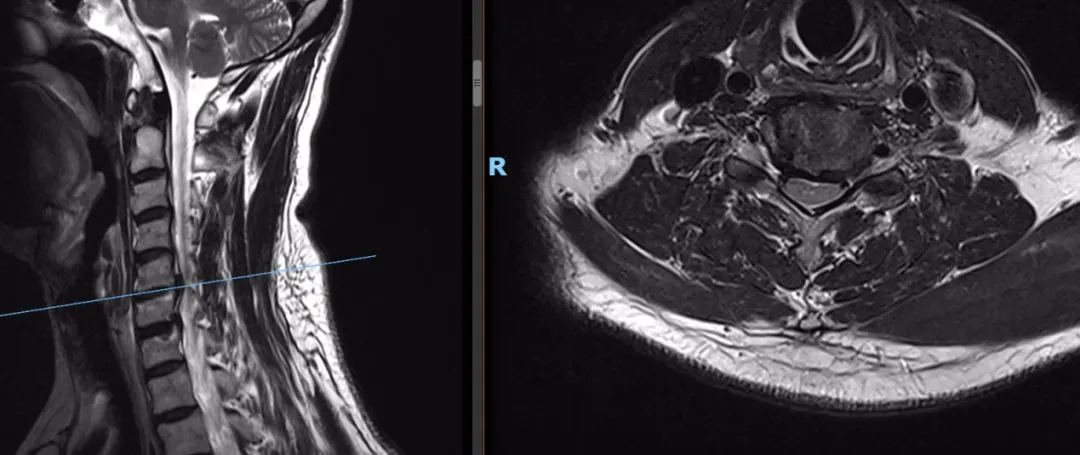

术前

骨科团队通过询问病史、查体及影像学表现后,考虑目前引起患者疼痛的原因是颈5-6节段突出。经过周密的术前计划和安排,骨科手术团队为患者实施了脊柱内镜下颈5-6椎间盘切除术,术中精准定位、仔细操作,精准摘除了突出的椎间盘组织,全程出血极少,未损伤脊髓、神经。